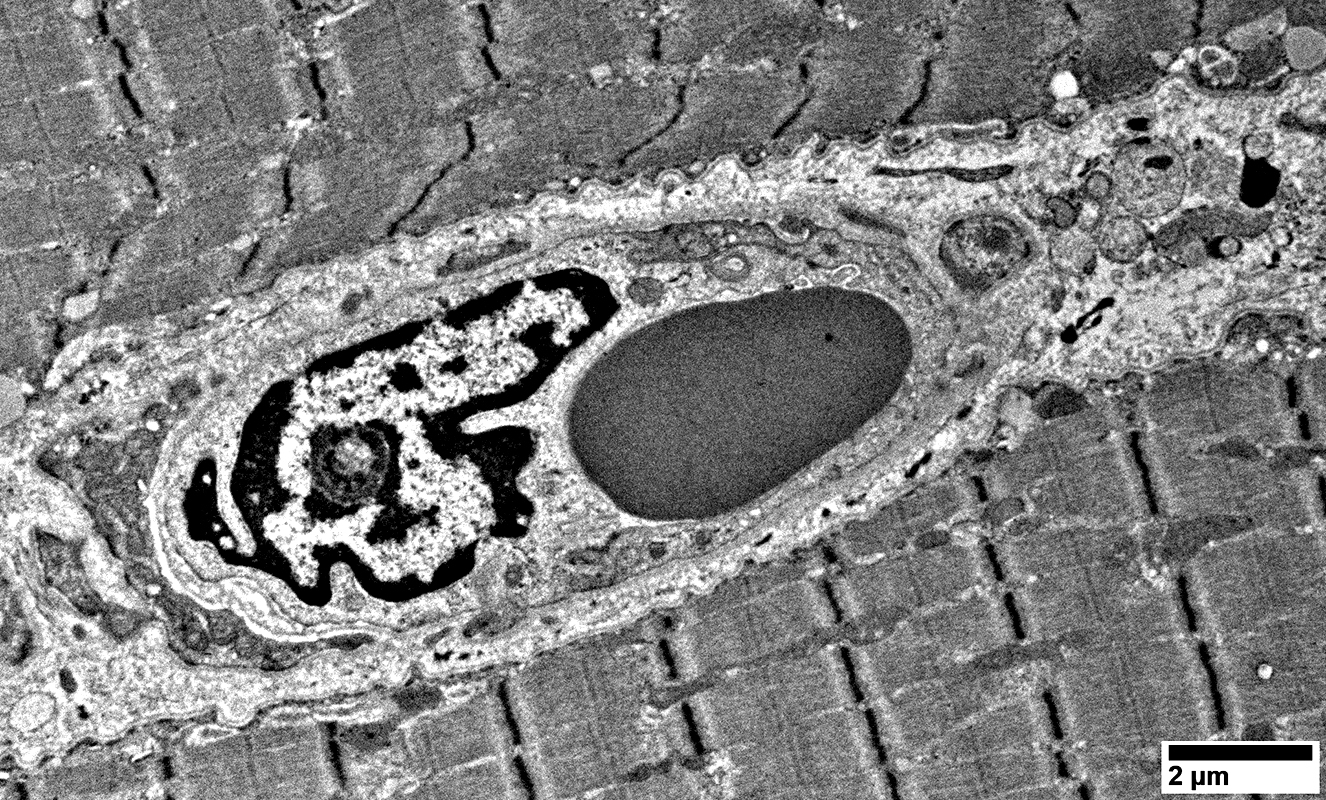

Sarcomere structure

Normal

Mitochondria

Often large

Abnormal pericytes in capillary wall

Cell, probably lymphocyte, below capillary

Damaged endomysial capillary

Damaged Capillary

No lumen

Endothelial cell with cytoplasmic vesicles inside a basal lamina

Small cell with many mitochondria below irregular capillary

Extracellular vesicular debris